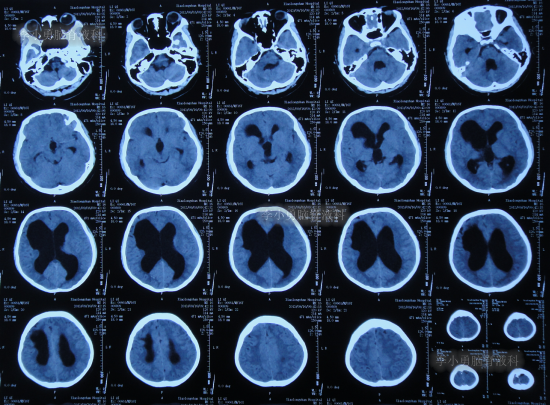

发现脑积水8年后即2013年9月16日,复查头颅CT示脑积水(图-1),没有相关症状,建议定期复查。

图-1:2013年9月16日头颅CT